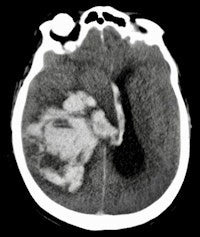

Dr. Wolter Oosterhuis from Rotterdam.The advantages of the minimally invasive method included perfect depiction of pathologies such as pneumonia, sometimes overlooked in traditional autopsy due to the thickness of organ slices. In addition, MRI appeared highly sensitive for guiding tissue sampling in the diagnosis of acute myocardial infarction. However, the minimally invasive approach had trouble identifying bowel ischemia, because it is difficult to spot early necrosis in the bowel wall or obtain samples when it can be seen.